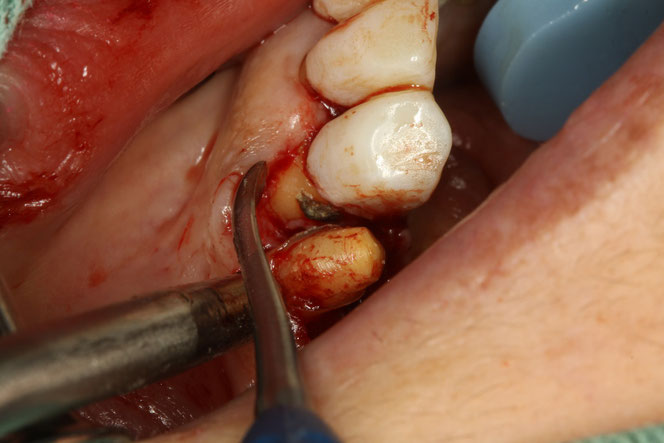

治療のポイントは“順番”

このような場合、

✔ 虫歯の除去

✔ 歯ぐきの再生治療

を組み合わせて行います。

単にレジン(白い詰め物)で埋めるだけでは、

再び虫歯になる可能性があります。

露出した根を歯ぐきで覆うことで、